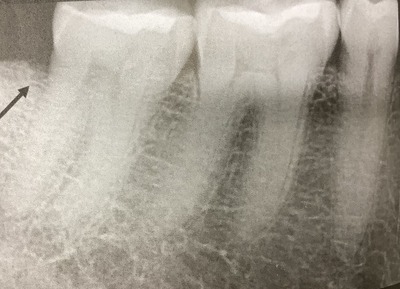

歯の上から入るヒビ、クラックはよく近遠心に入る。

前から後ろ方向にです。

で、レントゲンの撮影方向と平行なので、普通のレントゲンでは写りにくいです。

で、骨の溶け方から想像します。